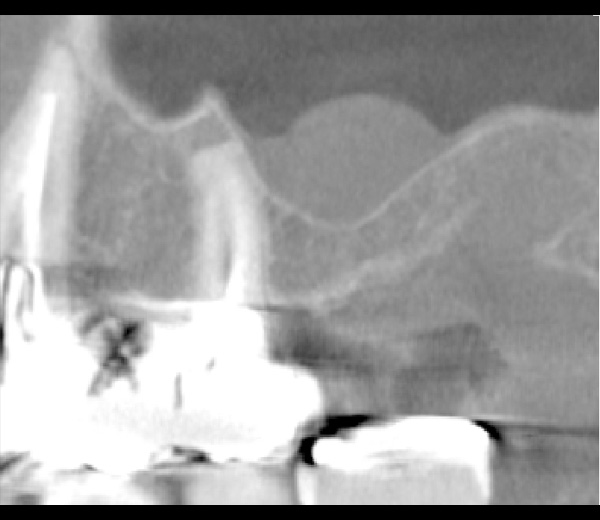

| 年代・性別 | 50代 男性 |

|---|---|

| 主訴 | 右下の歯が割れてしまったのでインプラントをして欲しい |

| 治療期間 | 約6ヶ月 |

| 費用 | 1,100,000円 |

| 治療内容 | インプラント、骨造成、結合組織移植、セラミック修復 |

| 治療に伴うリスク | インプラント周囲炎 セラミックの破折、脱離 |

*キャンセルポリシーをご一読のうえご予約ください